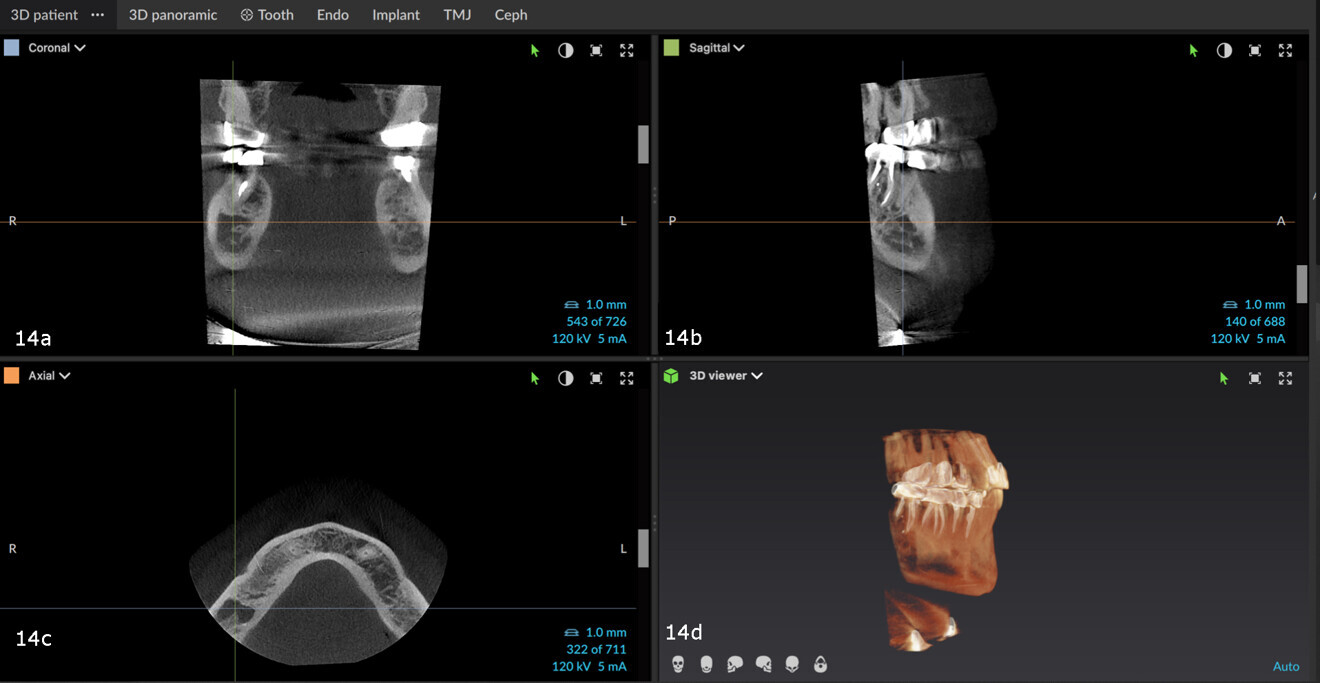

Figs. 4a–d: After adjusting the axial view according to the roots, the extent of the lesions and the separation between the lesions could be seen clearly.

Figs. 14a–d: Bone lesion with a non-uniform border or shape on the CBCT scan.

The patient in this case was referred back to check on a retreatment performed some years before. It was clear from the radiographs that the periapical area of the molar was not healthy (Figs. 13a & b). A CBCT scan was taken and, when studied in DTX software, showed a lesion under the molar (Figs. 14a–d). After a careful study of the case, it was determined that the lesion was unrelated to the apices, the periodontal ligament was not interrupted and the lesion had no clear epithelial lining. In order to establish the aetiology, the patient was asked about pain on chewing, but reported no discomfort whatsoever. He had also not been involved in a fight, but recalled having slipped when taking a shower and having hit his mandible on the bathtub.